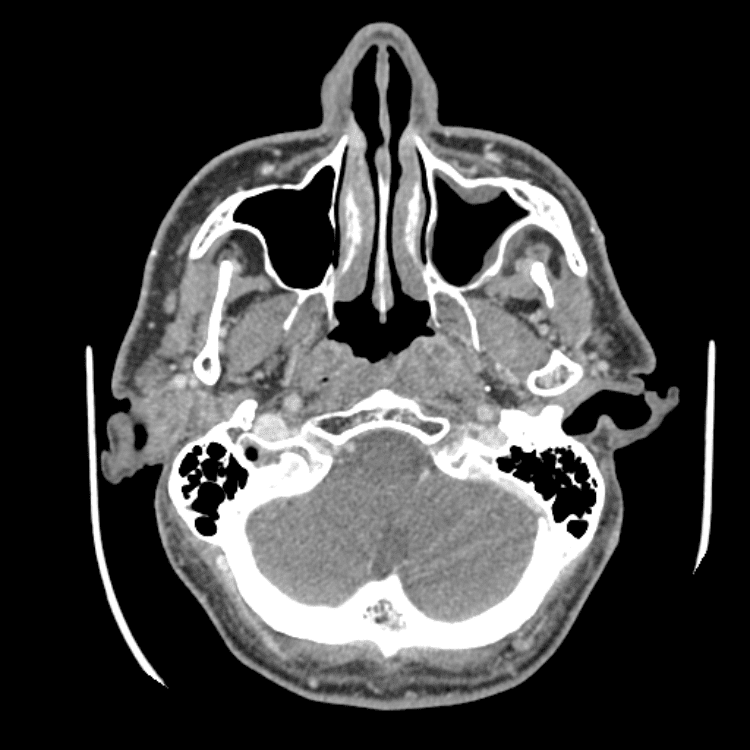

Head and Neck

Practice

Simulates call by including subtle or difficult cases and some normals.

27 cases